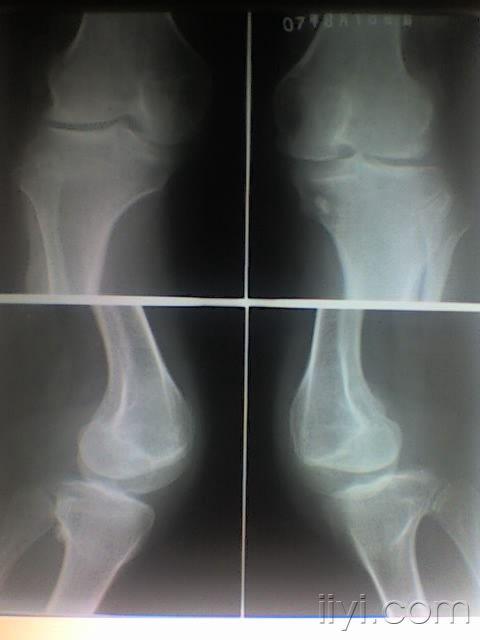

正常的膝关节影像图片

正常的膝关节影像图片,正常膝关节x线图片

正常膝关节x线图片

正常膝关节x光片图

正常的膝关节x片图片

正常膝关节x光片

正常膝关节x片